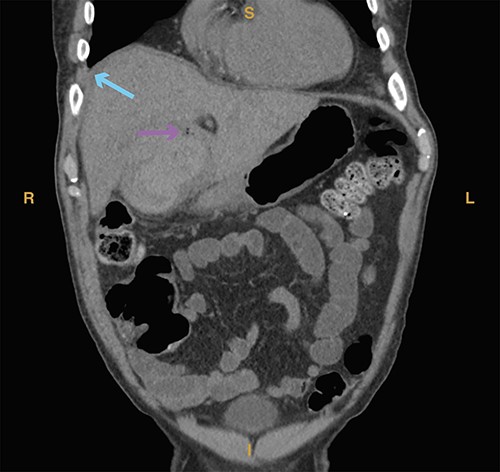

A 74-year-old man with a past medical history of type II diabetes mellitus, recent COVID-19 infection with prolonged hospital course and ventilator dependence requiring tracheostomy status post decannulation, coronary artery disease and myocardial infarction status post three-vessel coronary artery bypass graft in 1991 and drug-eluting stent placement in 2020 on dual antiplatelet therapy (DAPT; aspirin and clopidogrel) presented with acute onset epigastric and right upper quadrant pain that started 3 hours prior to presentation from a rehabilitation facility. In the emergency department, the patient was hypotensive (systolic blood pressure of 70 mmHg) with a transient response to crystalloid resuscitation. Laboratory studies revealed a hemoglobin of 8.9 g/dl, a hematocrit of 27%, leukocytosis (21.6 × 103/μl, normal range 4.3–10.8 × 103/μl), slightly elevated lactic acid to 1.9 mmol/L (normal range 0.3–1.9 mmol/l) and elevated creatinine serum to 1.43 mg/dl. Computed tomography of the abdomen and pelvis revealed a distended gallbladder containing multiple calculi and hyperdense intraluminal content (Fig. 1A). A prominent tortuous cholecystic artery branch was noted at the fundus (Fig. 1B). Hemoperitoneum with concern for acute hemorrhage was suspected, given fluid collection in the pericholecystic, perihepatic and perisplenic spaces.

(A) Computed tomography imaging from Case 1 showing a distended gallbladder with multiple calculi (cyan arrow) as well as hyperdense intraluminal fluid (magenta arrow) with collection in the pelvis (green arrow) consistent with hemorrhage. Present in the figure, the letters S, L, I and R denote superior, left, inferior and right, respectively. (B) Computed tomography imaging from Case 1 showing the tortuous path of a cholecystic artery branch (magenta arrow) at the gallbladder fundus. Present in the figure, the letters A, L, P and R denote anterior, left, posterior and right, respectively.